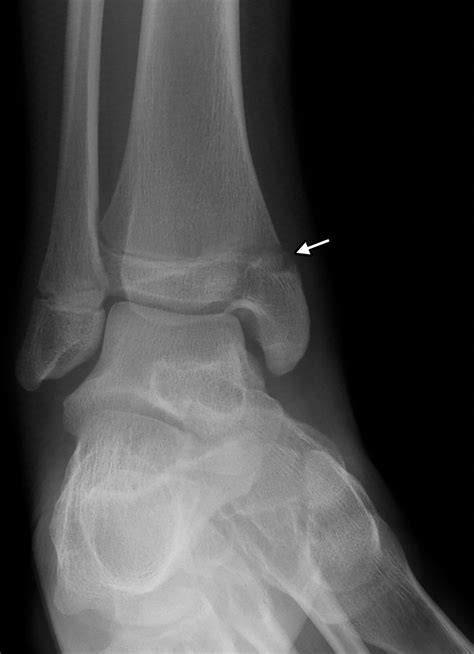

A hairline fracture, also known as a stress fracture, is a thin crack in the bone. In the case of a hairline fracture ankle, this crack typically occurs in one of the three bones that form the ankle joint: the tibia, fibula, or talus. These fractures are often caused by repetitive stress or a sudden impact, such as twisting the ankle or landing awkwardly after a jump.

Diagnosing a hairline fracture ankle involves a combination of physical examination and imaging tests. Your healthcare provider will likely perform the following steps:

• Physical Examination: The doctor will assess the affected area for swelling, tenderness, and range of motion.

• Imaging Tests: X-rays are the most common imaging test used to diagnose fractures. However, hairline fractures may not always be visible on initial X-rays. In such cases, additional imaging tests such as MRI or CT scans may be required.

In some cases, a bone scan may be recommended to detect stress fractures that are not visible on X-rays. This test involves injecting a small amount of radioactive material into the bloodstream, which is then detected by a special camera.